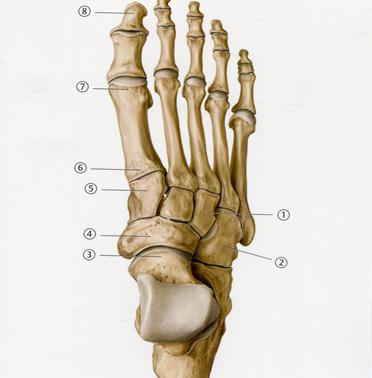

39. Төменде көрсетілген суреттегі белгіленген № 3 сүйекті

А. Қайықша

В. Латеральды сына тәрізді

С. Медильді сына тәрізді

D. Текше

+Е. Топай

53. Төменде көрсетілген суреттегі белгіленген № 5 сүйекті атаңыз.

А. Алақан сүйегі

В. Біз тәрізді өсінді

+С. Қайықша тәрізді

D. Үш қырлы

Е. Ілмек тәрізді